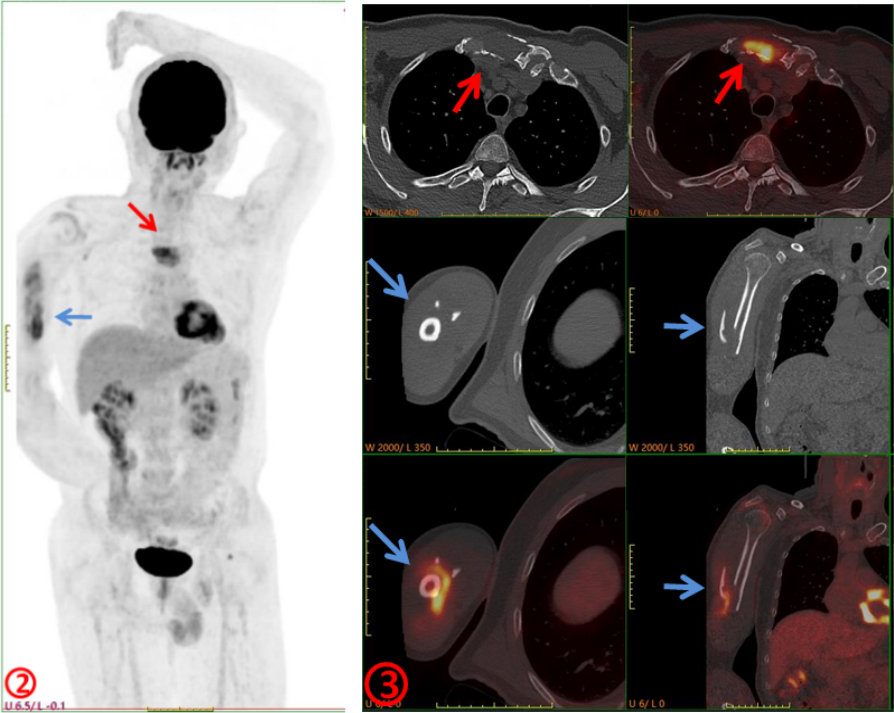

臨床初步診斷為惡性腫瘤骨轉(zhuǎn)移,遂行PET/CT進(jìn)一步檢查,示右側(cè)肱骨(圖2、3,藍(lán)箭)、胸骨(圖2、3,紅箭)骨質(zhì)破壞并代謝增高,SUVmax約6.0,余未見其它明顯異常病灶,考慮骨原發(fā)腫瘤(圖2)。隨后完善胸骨病變穿刺活檢及骨髓穿刺,病理示多發(fā)性骨髓瘤。

本例患者臨床初診考慮肱骨轉(zhuǎn)移,行PET/CT檢查目的是為了查找“原發(fā)灶”,以進(jìn)一步明確診斷及分期,指導(dǎo)后續(xù)治療。但PET/CT除肱骨病變外還發(fā)現(xiàn)了常規(guī)影像學(xué)沒發(fā)現(xiàn)的胸骨病變,同時(shí)未發(fā)現(xiàn)確切的原發(fā)臟器腫瘤,綜合考慮為骨原發(fā)惡性腫瘤,指導(dǎo)臨床進(jìn)行穿刺活檢,最終病理證實(shí)為多發(fā)性骨髓瘤。PET/CT是功能顯像,從代謝的角度提供信息,將可疑之處點(diǎn)亮,讓不起眼的病灶脫穎而出;同時(shí)是全身顯像,可以“一目了然”地了解全身各臟器組織的葡萄糖代謝情況,為診斷帶來新的思路,對腫瘤臨床分期、預(yù)后評(píng)估更準(zhǔn)確。